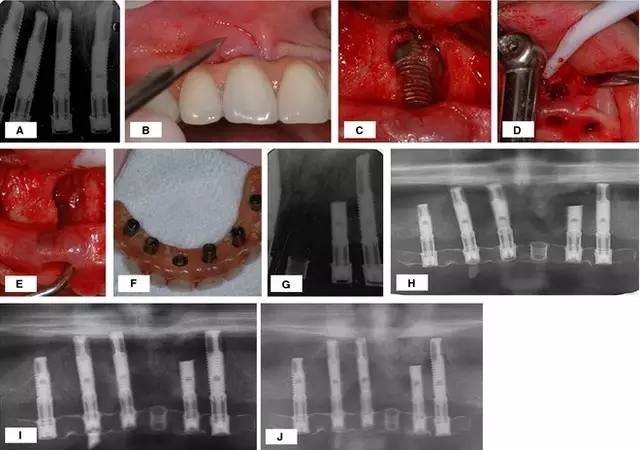

對于種植體周圍炎引起的骨缺損,有學(xué)者應(yīng)用骨替代材料取得了很好的治療效果。Quirynen 等應(yīng)用去蛋白的牛骨粉成功的治愈了種植體周圍炎引起的骨缺損,治療方法如圖 1。

圖 1 :(A)患牙拔除三月后根尖周 x 線片; (B) 種植體植入三月后出現(xiàn)根尖周病變 ;(C) 出現(xiàn)瘺管; (D) 翻起全厚黏骨膜瓣;(E –G) 骨缺損檢查,刮除病變組織,生理鹽水沖洗; (H) 植入骨替代材料,引導(dǎo)骨再生; (I)術(shù)后 4 個(gè)月口內(nèi) x 線片,基臺連接 ;(J,K)負(fù)載一年后